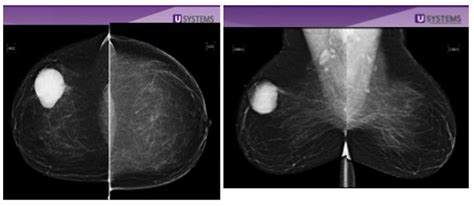

Are Your Breasts Dense? | The GW Cancer Center from cancercenter.gwu.edu Tumors can be cancerous or benign. These are breast benign tumors. Mammograms will often detect areas that are most of them: A doctor with special training, called a radiologist, will read the mammogram. Why do i need a mammogram? The main advantage of dbt is its potential to improve the sensitivity and specificity of mammography. The following are just a few examples of the variety of mammogram images a radiologist may encounter and how they are interpreted. A mammogram can be used either for screening or for diagnostic purposes.

So, that would be like an ultrasound because they can see the lump, they can see its consistency. The following are just a few examples of the variety of mammogram images a radiologist may encounter and how they are interpreted. And that's research we're proposing to do, is to look at some indications for ct imaging and see when it really does have a benefit that outweighs the risk. Mammograms will often detect areas that are most of them: A doctor with special training, called a radiologist, will read the mammogram.

And that's research we're proposing to do, is to look at some indications for ct imaging and see when it really does have a benefit that outweighs the risk. The look of breast cancer on a mammogram. If breast cancer is picked up by further tests. Tumors may be benign or fibroadenomas: These are breast benign tumors. Like many women, she mistakenly believed it was the most appropriate way to prevent breast cancer. Calcifications are mineral deposits that look like white spots on a mammogram. So the use of mammograms could increase cancer slightly, but the benefits of mammograms in women 50 and over outweigh the risk. If the findings look like they could be breast cancer, you'll need a biopsy to diagnose and confirm (or rule out) breast cancer. A doctor with special training, called a radiologist, will read the mammogram. If the tumor is benign, this is not a health risk and it is unlikely to. Dr sarah jarvis mbe if a mammogram is abnormal, further tests will be needed. On a mammogram, fatty tissue looks dark, while dense tissue looks white, like tumours, so it can hide a tumour.